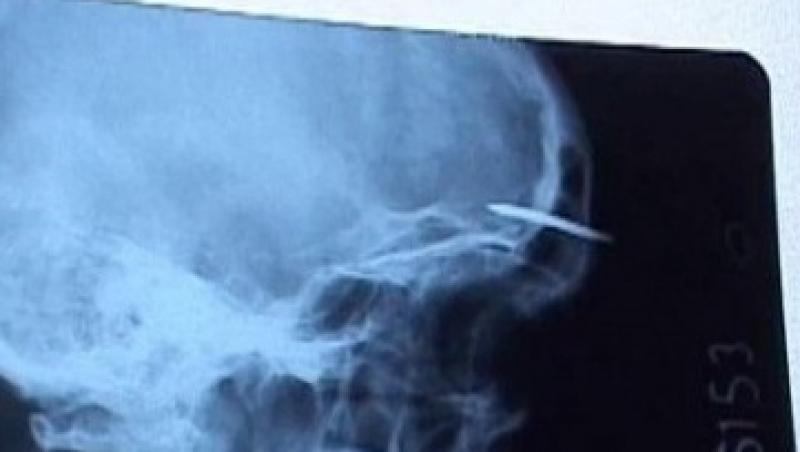

Un deținut din Penitenciarul Gherla a încercat să se automutileze cu un cui pe care a reușit să și-l înfingă în frunte. Deținutul a fost dus de urgență la spital, unde a primit îngrijiri medicale, iar viața nu îi este pusă în pericol.

Conform autorităților penitenciarului, deținutul se afla în evidența cabinetului medical cu afecțiuni psihice, notează Cluj24. În momentul în care a fost transportat din celulă spre cabinetul medical, medicii de acolo au constatat că bărbatul și-a bătut singur un cui în frunte în scopul automutilării.